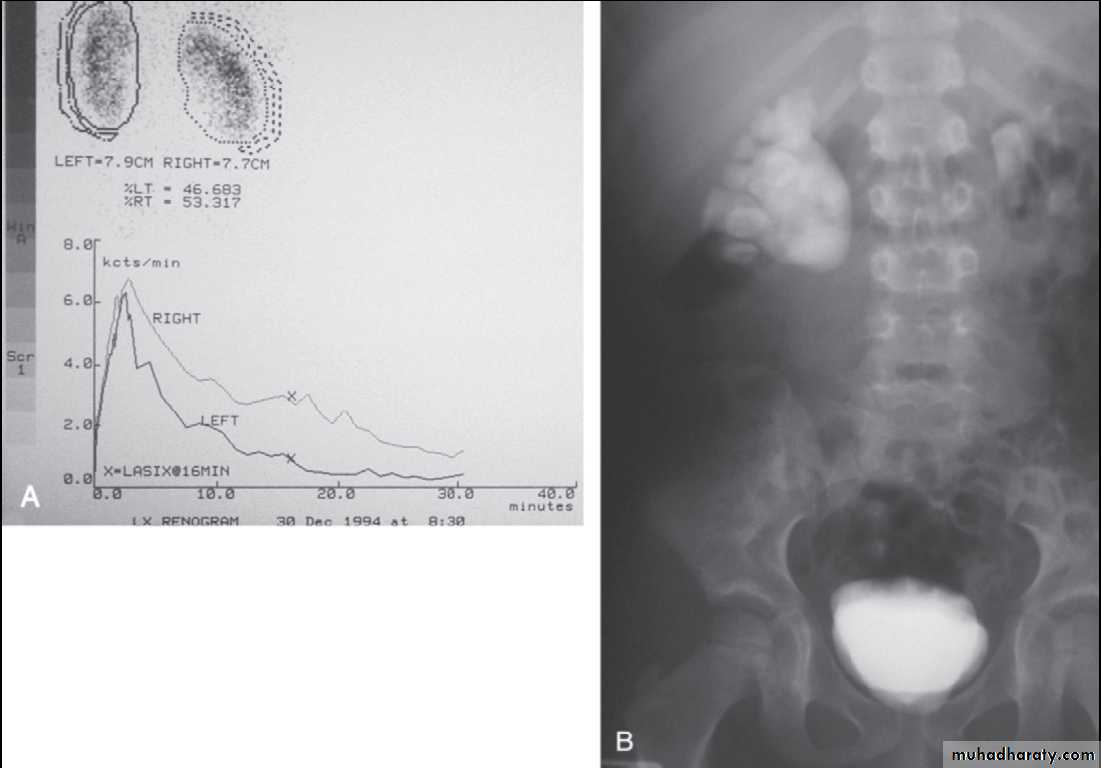

Obstruction of ureteropelvic junction

(PUJ obstruction)PUJ obstruction is probably the most common congenital abnormality of the ureter

It is seen more often in boys than girls (2:1 ratio) &, in unilateral cases more often on the left than right side (5:2 ratio)

Diagnosis

IVP (diagnostic)